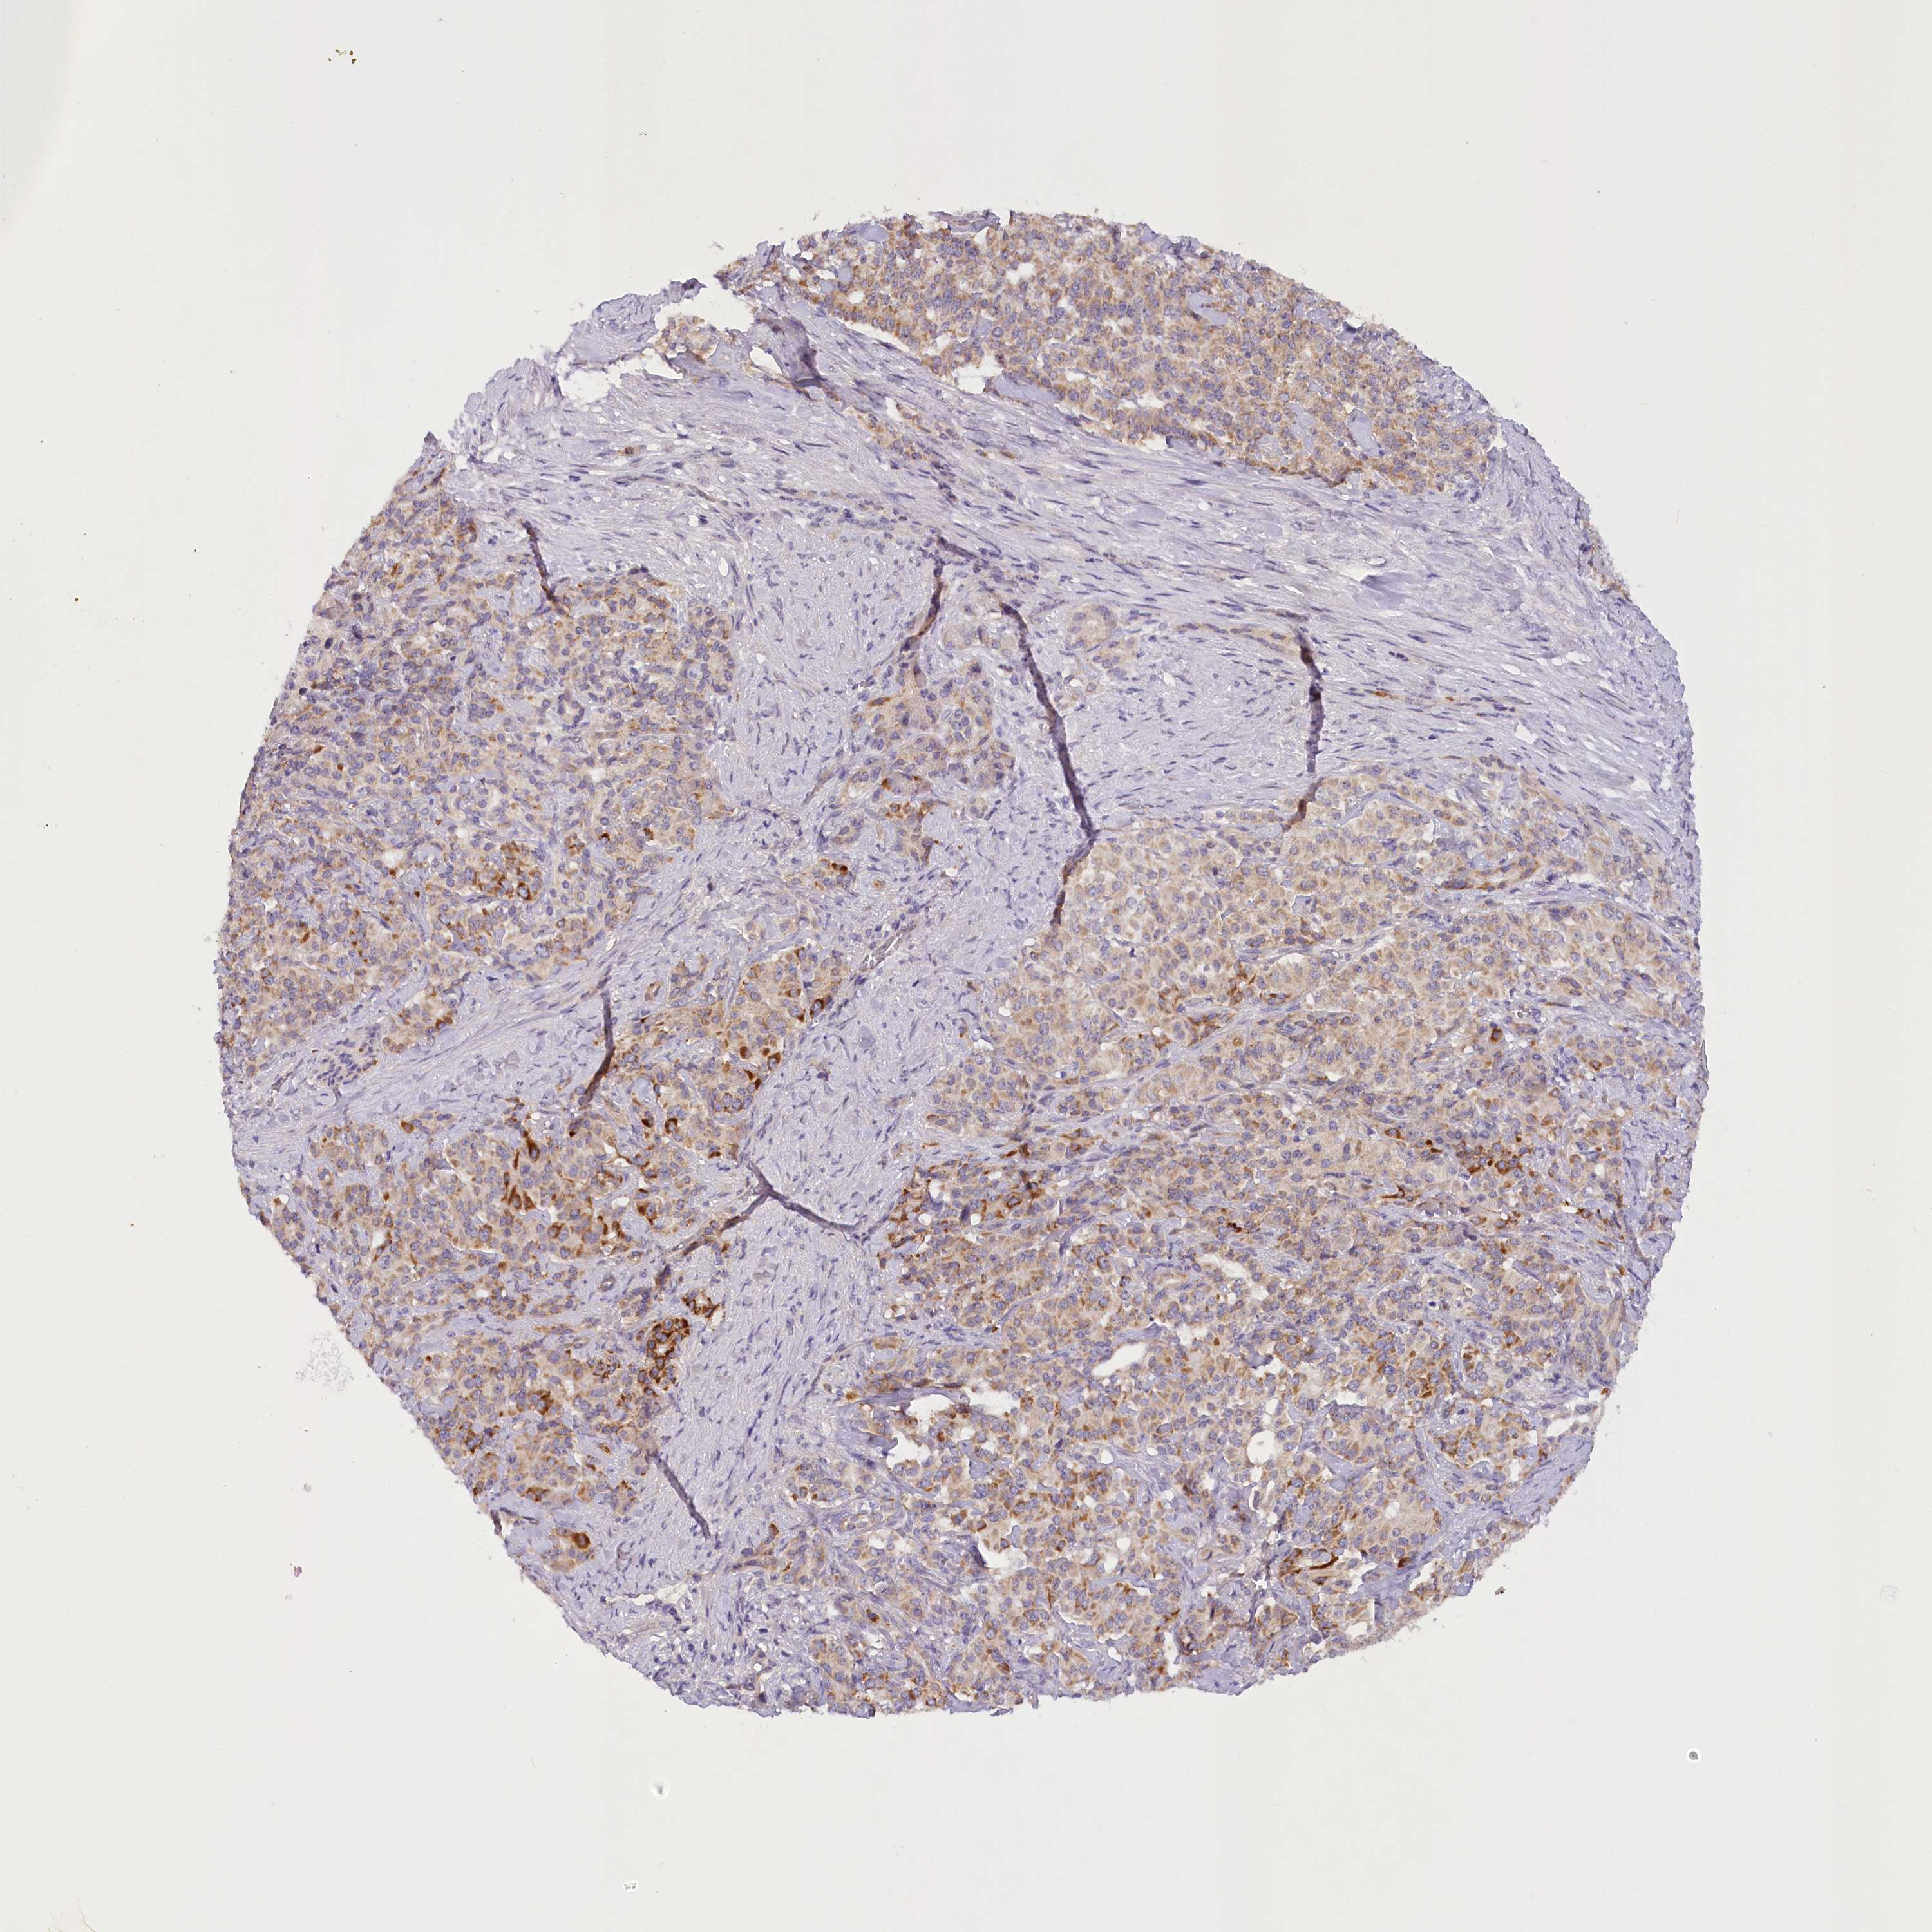

PANCREATIC CANCER - Protein expressioni

A mouse-over function shows sample information and annotation data. Click on an image to view it in a full screen mode. Samples can be filtered based on level of antibody staining by selecting one or several of the following categories: high, medium, low and not detected. The assay and annotation is described here.

Note that samples used for immunohistochemistry by the Human Protein Atlas do not correspond to samples in the TCGA dataset.

Antibody stainingi

Antibody staining in the annotated cell types in the current human tissue is reported as not detected, low, medium, or high, based on conventional immunohistochemistry profiling in selected tissues. This score is based on the combination of the staining intensity and fraction of stained cells.

Each image is clickable and will lead to virtual microscopy that enables deeper exploration of all samples and also displays staining intensity scores, fraction scores and subcellular localization as well as patient and tissue information for each sample.

Antibody HPA035911

Staining

High

Medium

Low

Not detected

Intensity

Strong

Moderate

Weak

Negative

Quantity

>75%

75%-25%

<25%

None

Location

Nuclear

Cytoplasmic/membranous

Cytoplasmic/membranous,nuclear

Adenocarcinoma, NOS